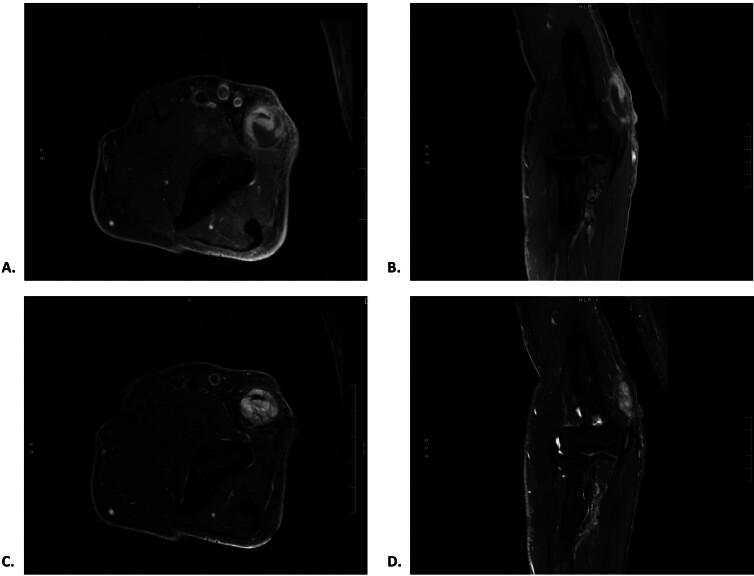

Peripheral nerve masses have a wide differential diagnosis; however, there is no established diagnostic framework for evaluating non-neoplastic etiologies, such as inflammatory or infectious lesions. Here, we present a rare case of an ulnar nerve granuloma that initially mimicked a peripheral nerve sheath tumor (PNST) on imaging and clinical presentation to elucidate the relevant medical history, imaging, and histology that aid in distinguishing inflammatory, infectious, and neoplastic peripheral nerve lesions. An 85-year-old man with melanoma and multiple prior right elbow surgeries presented with right-hand weakness and a rapidly enlarging gadolinium-enhancing ulnar nerve mass suggestive of a PNST that warranted surgical resection. Surgical histology showed a necrotizing granulomatous lesion that then became most concerning for a parasitic infection. However, broad serum and histologic testing by the Centers for Disease Control and Prevention were all ultimately negative. The final diagnosis was an inflammatory reaction to a retained foreign body from his prior elbow surgeries. In summary, surgery and comprehensive histologic workup are required for diagnosing granulomatous peripheral nerve lesions that mimic PNSTs on imaging and infection on histology.

Abstract Image